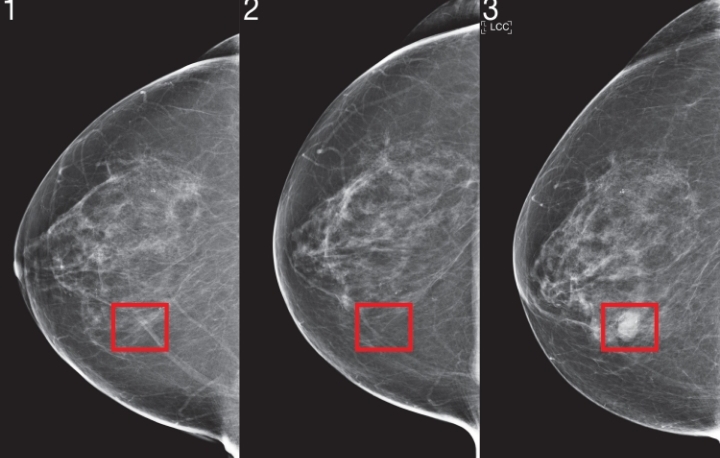

Robust artificial intelligence tools to predict future cancer. Image Source: MIT News Massachusetts Institute of Technology

The new AI systems flip the script. They use deep learning—a subset of artificial intelligence trained on massive datasets of mammograms paired with years of follow-up data. For instance, Clairity Breast was trained on millions of images linked to five-year outcomes. MIT’s Mirai model drew from over 60,000 mammograms and has since been validated on more than 1.9 million scans across 21 countries.

The AI doesn’t just look for obvious masses or calcifications. It analyzes micro-patterns in breast tissue: tiny changes in density, asymmetry between breasts, vascular patterns, and textural anomalies that signal future risk. In studies, AI scores were significantly higher in breasts that later developed cancer—even four to six years prior—compared to cancer-free ones. One analysis using a commercial AI (INSIGHT MMG) showed predictive power up to six years out, with scores doubling in at-risk tissue long before diagnosis.

Consider side-by-side mammograms from MIT research: an early scan might look “normal” to a doctor, but the AI flags a faint irregularity (highlighted in red). Years later, that same area reveals a tumor. Saliency maps—heatmaps generated by the AI—highlight exactly where the model sees risk, providing radiologists with explainable insights.